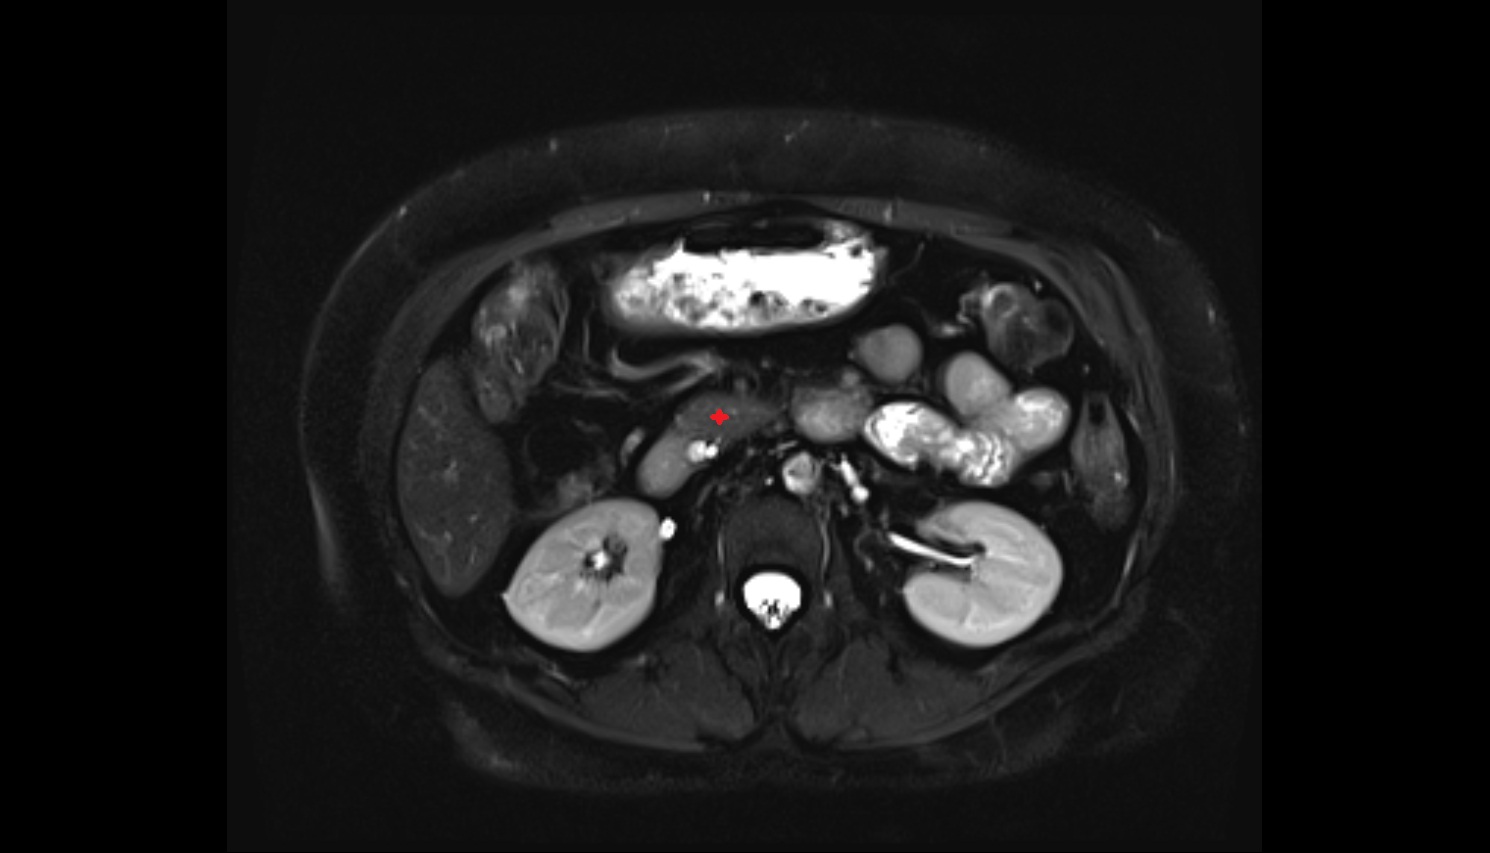

- kidneys

- Right kidney

- Left kidney

- Kidney cortex (Renal cortex)

- Renal medulla

- Renal pyramids

- Renal fascia

- Renal artery

- Renal vein

- Left renal vein

- Right renal vein

- Renal pelvis